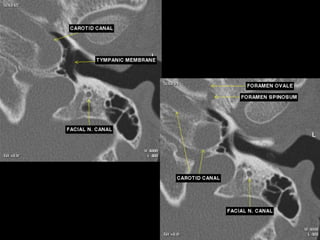

Coronal temporomandibular joint level

 The horizontal carotid canal is seen as an

oval structure just

lateral to petrooccipital suture.

 The semicanal for the tensor tympani

muscle is seen as a small

lucency lateral to the carotid canal.

 The air-filled eustachian tube is inferior to

the tensor tympani,

and the TMJ is seen laterally